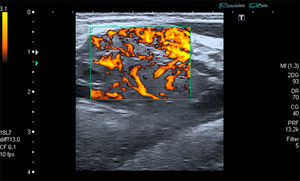

The patient was a 53-year-old man with no significant medical history. He presented with a painless mass in anterior forearm, reporting no previous injury. Physical examination confirmed the presence of a hard, immobile mass measuring less than 1cm. He came to the rheumatologic examination room, where he underwent soft tissue ultrasound (Toshiba Aplio®300). A round mass measuring less than 1cm was observed. It was iso/hypoechoic on gray scale images, was moderately well-defined, and was joined to a vessel that fed it (Fig. 1). On color Doppler, there was high echo intensity throughout the entire lesion, more intense on the periphery (Figs. 2 and 3). As there were findings that raised suspicion, such as heterogeneity, the marked vascularity and the marked Doppler signal (grade 3), magnetic resonance imaging was performed. This study revealed a round, well-defined form measuring 1cm, with hyperintensity on T1-weighted images, which pointed to a metastatic lesion (Fig. 4).